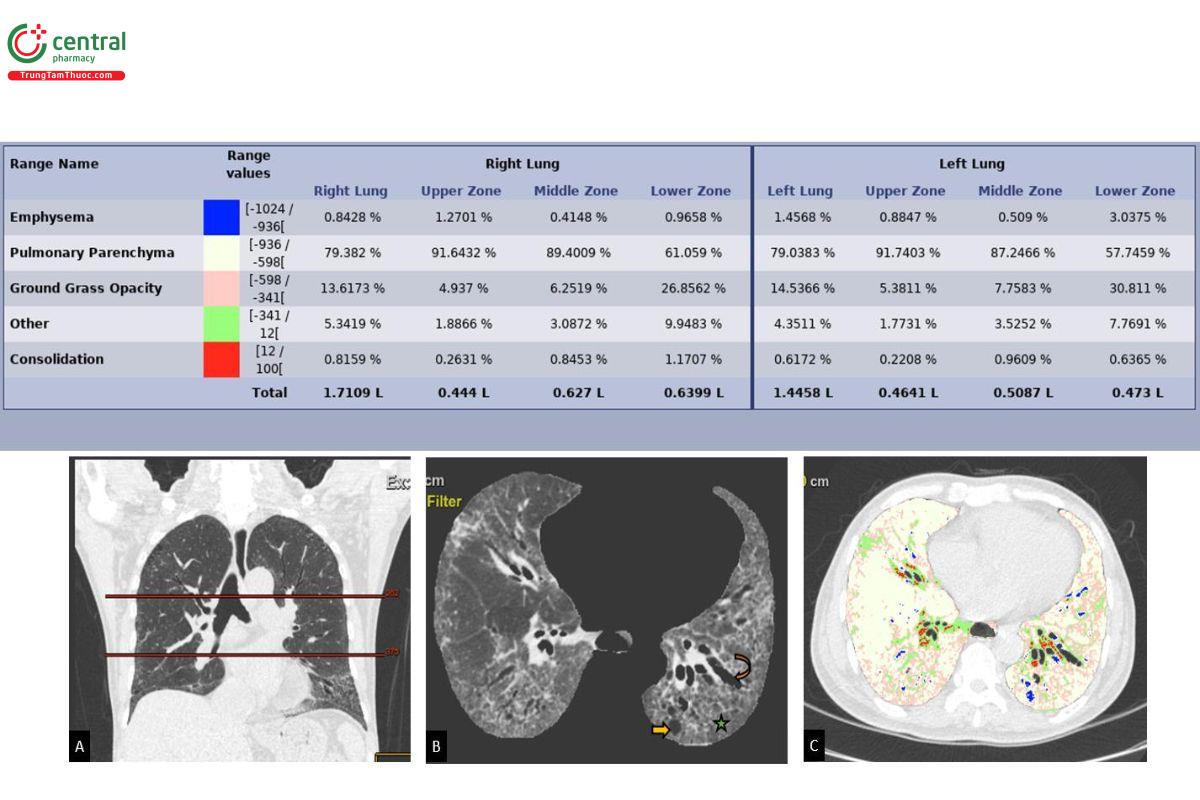

ILAs được mô tả là các bất thường chiếm hơn 5% vùng phổi bất kỳ (phân vùng phổi trên, giữa và dưới được xác định bằng bờ dưới cung động mạch chủ ngực và bờ dưới tĩnh mạch phổi dưới bên phải) (Hình 4A) [4]. Trong các mô tả ban đầu, ILA bao gồm các bất thường kính mờ hoặc lưới, nốt trung tâm tiểu thùy lan tỏa, giãn phế quản co kéo, tổ ong và kén khí (không bao gồm khí phế

thũng) (Hình 4B, C). Các nốt trung tâm tiểu thùy, là biểu hiện điển hình của viêm tiểu phế quản hô hấp [12] nên không được bao gồm vào ILAs vì đặc điểm này là phổ biến trong các hình chụp sàng lọc ung thư phổi ở bệnh nhân hút thuốc, thường không tiến triển và không liên quan đến xơ hóa. Mặc dù ngưỡng 5% mang tính ước lượng, nhưng được giữ lại để loại trừ các tổn thương tối thiểu và phù hợp với các y văn đã xuất bản trước đây. Bệnh lý xơ phổi màng phổi (pleuropulmonary fibroelastosis), đôi khi được phát hiện ngẫu nhiên trên CLVT, là một khái niệm độc lập không được ghi nhận là ILAs trong y văn [13].

Để hạn chế các sai số trên, các phần mềm định lượng tổn thương phổi (ví dụ Thoracic VCAR, GE Healthcare, Hoa Kỳ; Myrian, Intrasense, Pháp [28]) có tích hợp khả năng hiệu chỉnh các vùng đậm độ tổn thương tùy theo thực tế quan sát của bác sỹ có tiềm năng tăng độ chính xác trong chẩn đoán cũng như loại trừ ILAs (theo định nghĩa là các bất thường nhu mô chiếm tối thiểu 5% của phân vùng nhu mô phổi [4] (Hình 4).

![Hình 4. Bảng định lượng tổn thương phổi ở bệnh nhân bị ILD kiểu hình NSIP xơ hóa bằng ứng dụng Thoracic VCAR GE Healthcare. A: Các phân vùng phổi được giới hạn bởi mặt phẳng ngang qua bờ dưới cung động mạch chủ ngực và bờ dưới tĩnh mạch phổi phải (Hiroto, Lancet Respir Med, 2020,[3]). B: các hình ảnh kén khí dưới màng phổi (mũi tên thẳng), dãn phế quản (mũi tên cong), hình lưới (dấu sao). C: Hình ảnh phân vùng thương tổn nhu mô, gồm: Màu vàng: nhu mô phổi bình thường; Màu hồng: vùng kính mờ; Màu xanh lá: tổn thương xơ; Màu đỏ: các mạch máu; Màu xanh dương: khoảng khí.](/images/item/viem-phoi-ke-4.jpg)